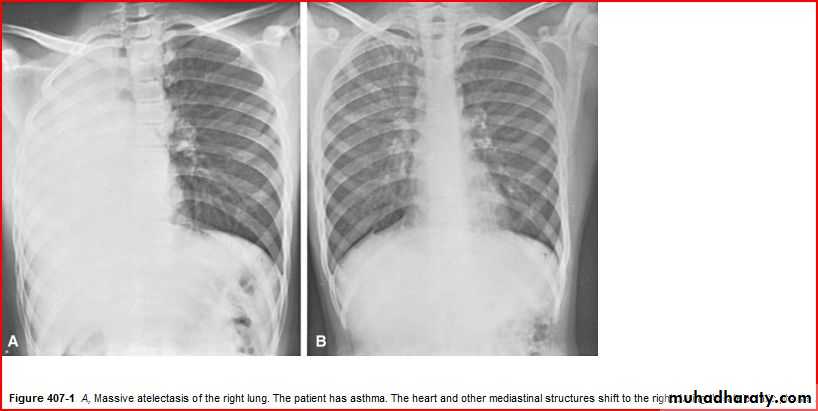

Homgenous opacity filling the rt. Hemithorax there is shefting in trachea to rt. Side mean this is collapse

Rt. Total lung collapse